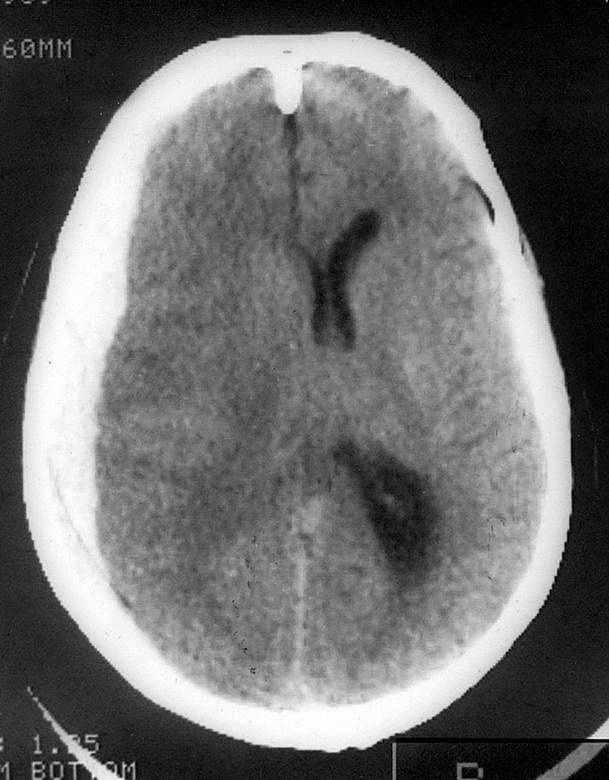

Иллюстрация к книге — 100 великих тайн сознания [i_012.jpg]

Патологические изменения в правой лобной доле мозга человека

Проведенное магнитно-резонансное сканирование мозга позволило установить, что у всех больных наблюдались серьезные дегенеративные изменения правой лобной доли.

С другой стороны, у пациентов с нормальными поведенческими стереотипами поражения нервной ткани в соответствующей зоне неврологи не обнаружили.

Все эти данные могут свидетельствовать о том, что значительная часть нашего самосознания подконтрольна определенной области, которая находится в правой лобной доле мозга. И любые патологические изменения этой зоны самым непосредственным образом сказываются на характере человеческой личности.